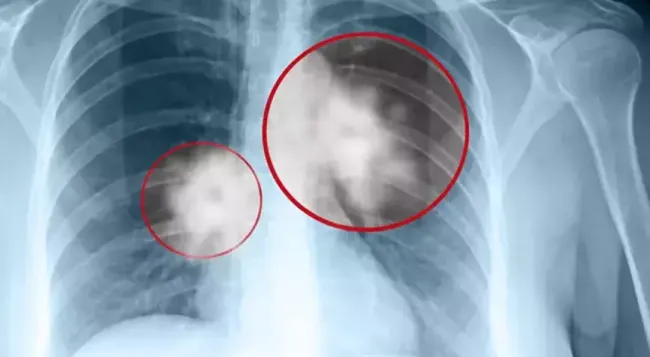

Erken Teşhis Hayat Kurtarıyor

Uzman, erken teşhisin son derece önemli olduğuna dikkat çekerek, “Erken teşhis konulduğunda önlenebilir ve tedavi edilebilir bir hastalık, yaklaşık yüzde 70 oranında sağ kalım mevcut. Çok erken tanı aşamasında yakalandığında ise bu oran yüzde 100’e kadar çıkabiliyor” ifadelerini kullandı.